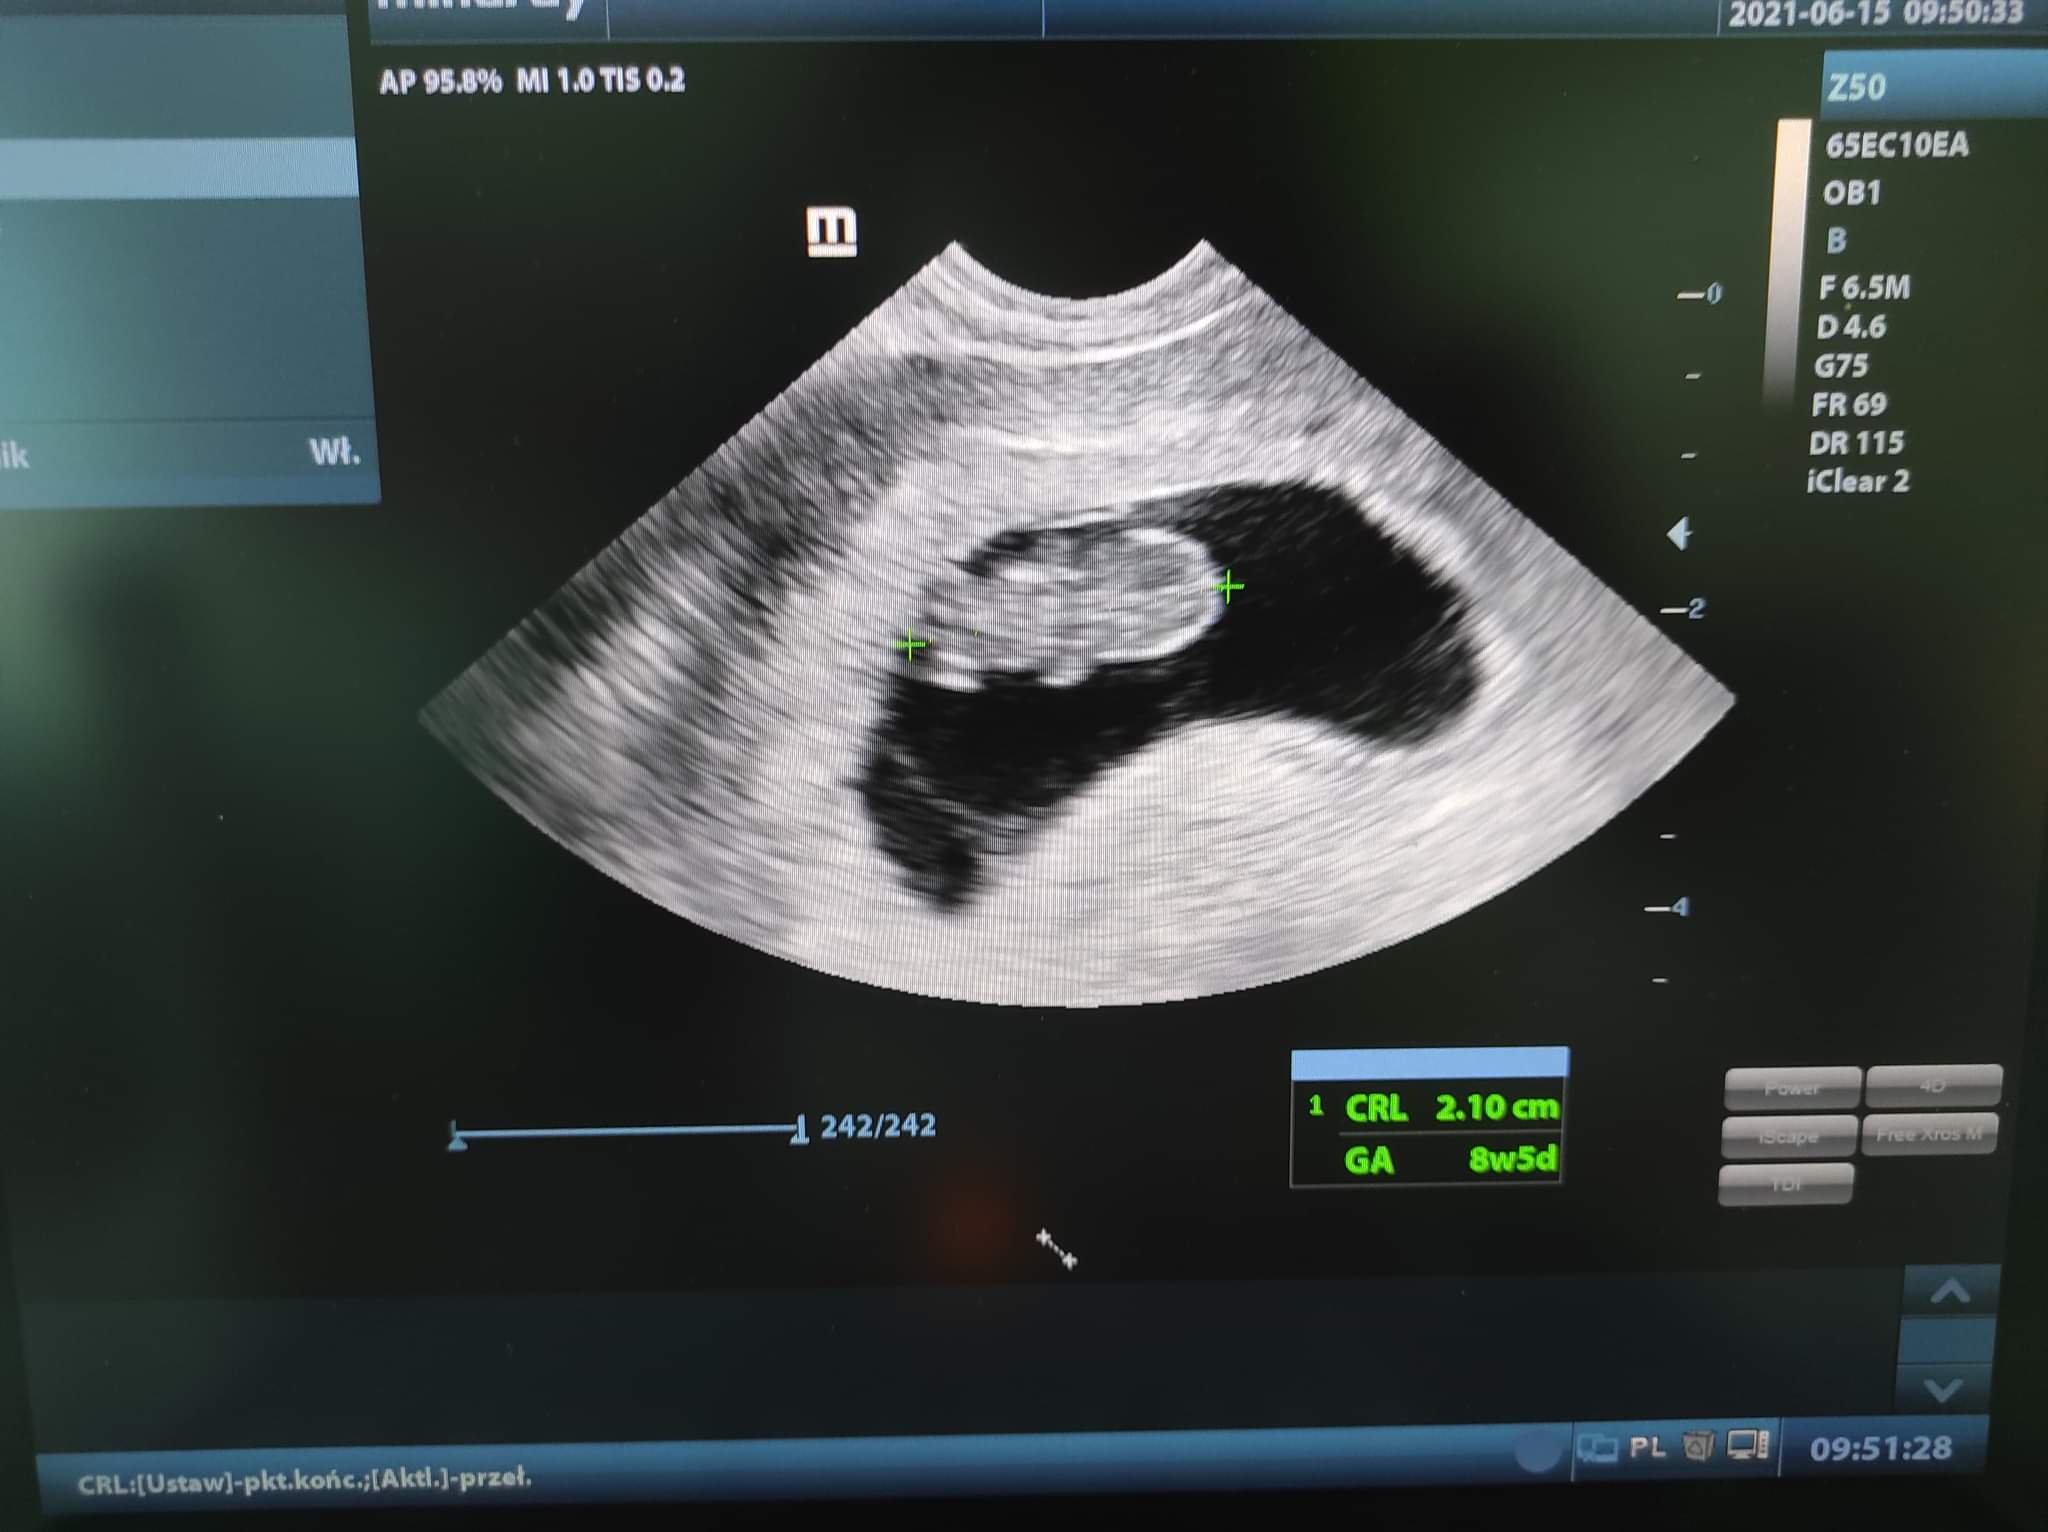

Z dzidziusiem wszystko dobrze, serce bije, wzrost z USG 10t4d a z miesiączki 10t3d, więc niemal idealnie

Załączam zdjęcie.